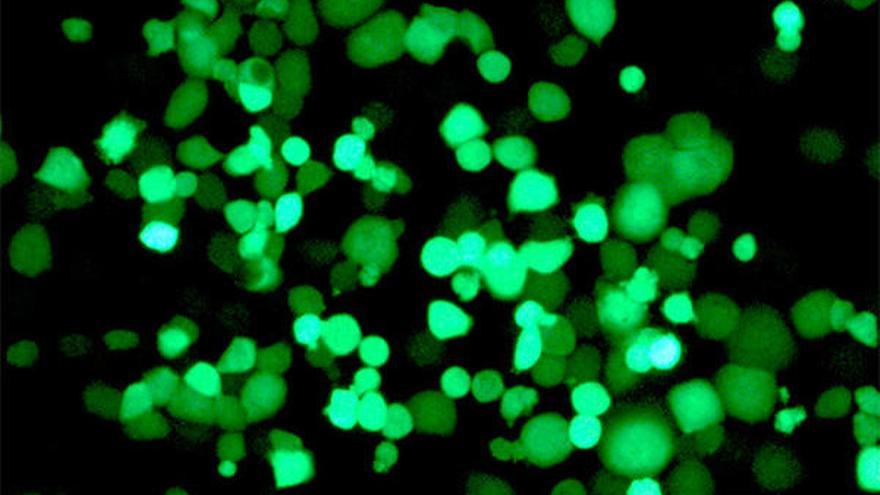

Para modificar el genoma de este virus, los investigadores insertaron secuencias que reconocen a las proteínas CPEB en regiones clave para el control de las proteínas virales, y comprobaron su actividad en modelos de in-vitro de cáncer de páncreas y observaron un control del crecimiento del tumor en ratones.

Los virus oncoselectivos creados son muy sofisticados porque se activan para CPEB4, pero se reprimen para CPEB1, con lo que los investigadores lograron una actividad viral atenuada en células normales, mientras que en las tumorales se mantiene o incluso aumenta la potencia de los virus.

"Cuando los virus modificados entran en las células tumorales, replican su genoma y, al salir, destruyen la célula liberando más partículas del virus, capaces de infectar, a su vez, a más células cancerígenas", ha señalado Fillat, que ha subrayado que "esta nueva aproximación es muy interesante, ya que se trata de una terapia que se amplifica de forma selectiva en el propio tumor".